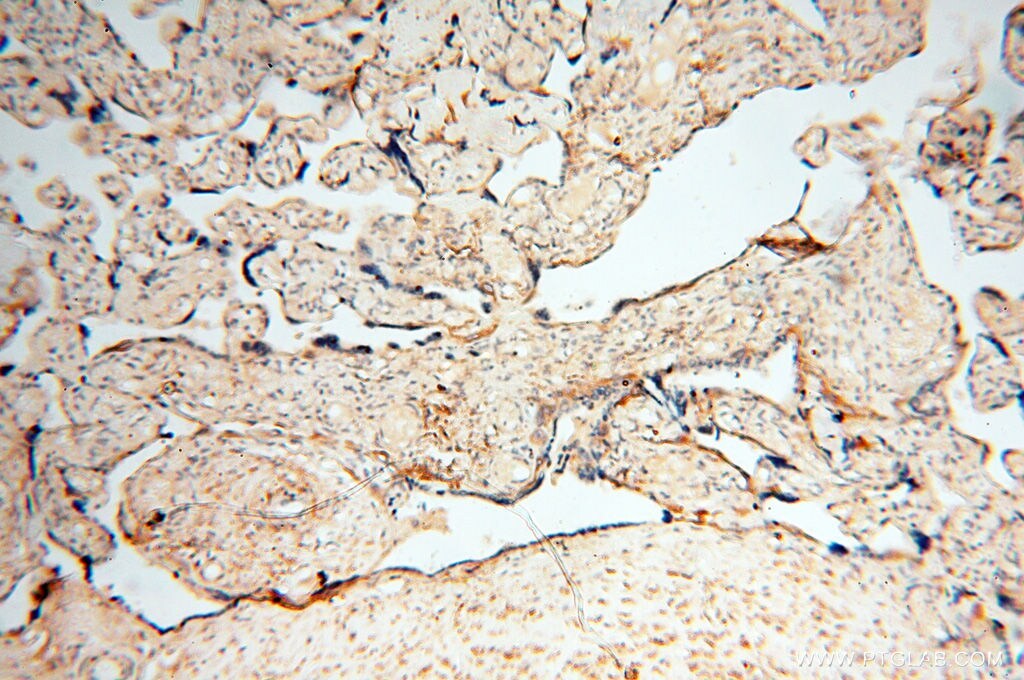

- Immunohistochemistry of paraffin-embedded human placenta using 17767-1-AP (USP38 antibody) at dilution of 1:50 (under 10x lens).

- Submitted by

- Immunohistochemistry of paraffin-embedded human placenta using 17767-1-AP (USP38 antibody) at dilution of 1:50 (under 40x lens).